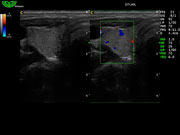

D7L40L 7.5МГц, линейный.

4.0МГц – 13.0 МГц. Применения: грудь, малые органы, нервы, сосуды, венозная катетеризация, мышцы и скелет, управление биопсией. |